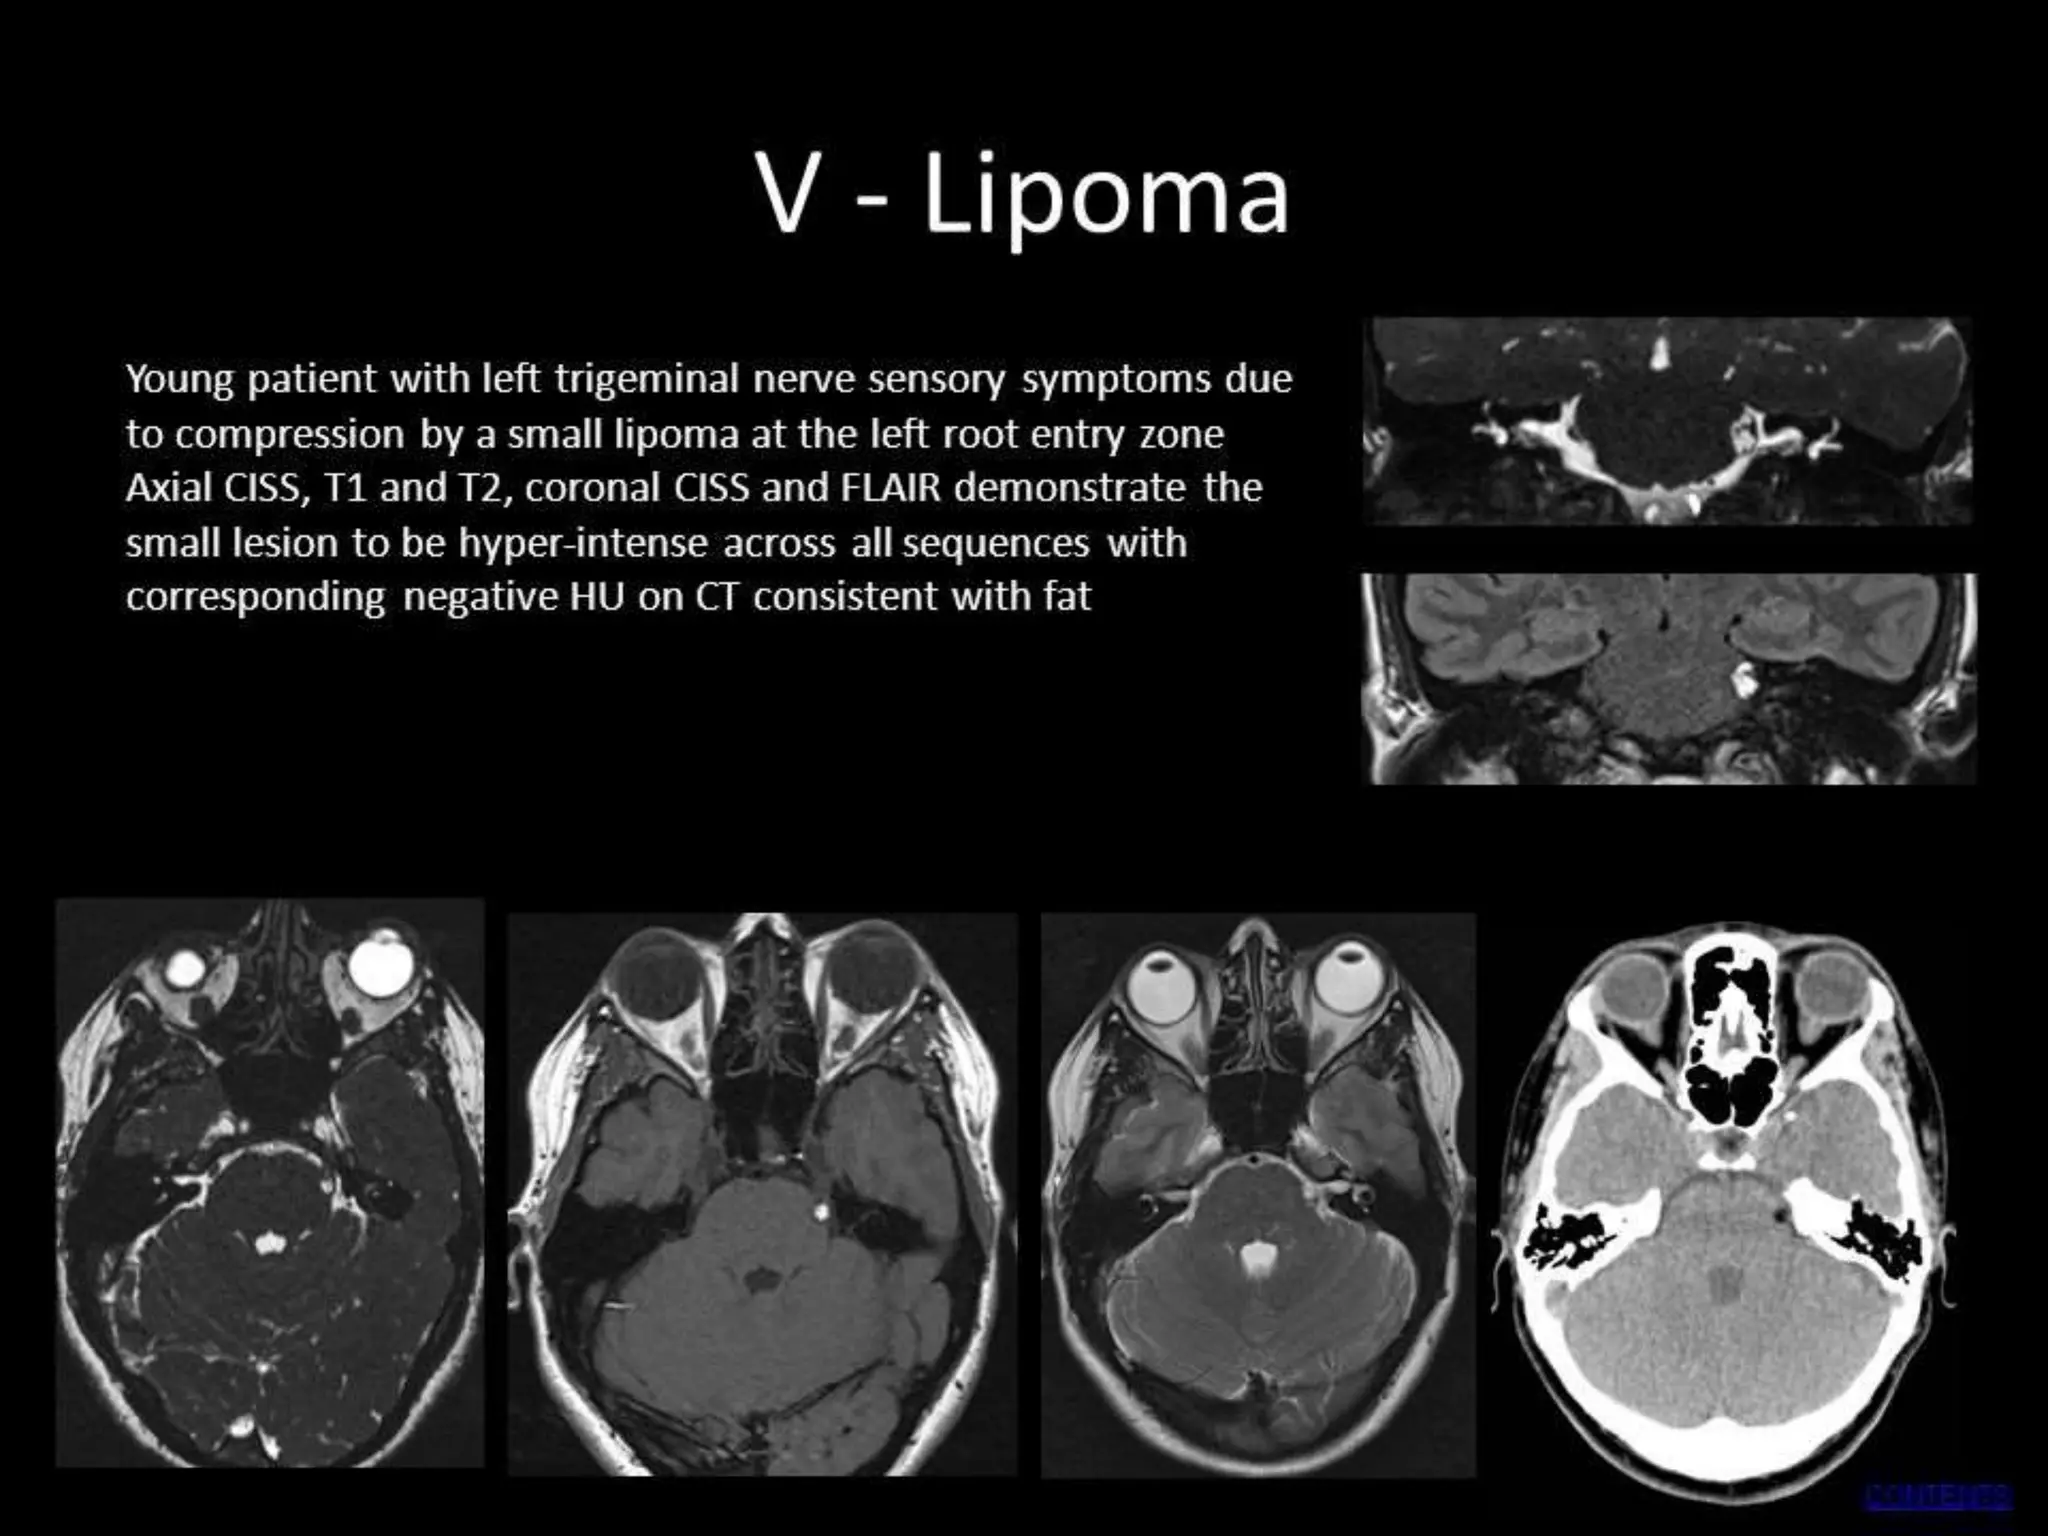

MULTIPLE SCLEROSIS:

A plaque of demyelination at the root entry zone of the trigeminal nerve